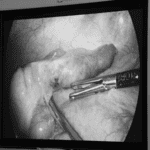

Ca mổ cấp cứu được tiến hành lúc gần nửa đềm và kết thúc sau đó 2 tiếng, khối máu tụ lớn trong cột sống cổ của chị được lấy bỏ, giải phòng chèn ép tuỷ thần kinh. Sau mổ chị thở yếu nên nằm hồi sức 3 ngày rồi chuyển về khoa phòng.